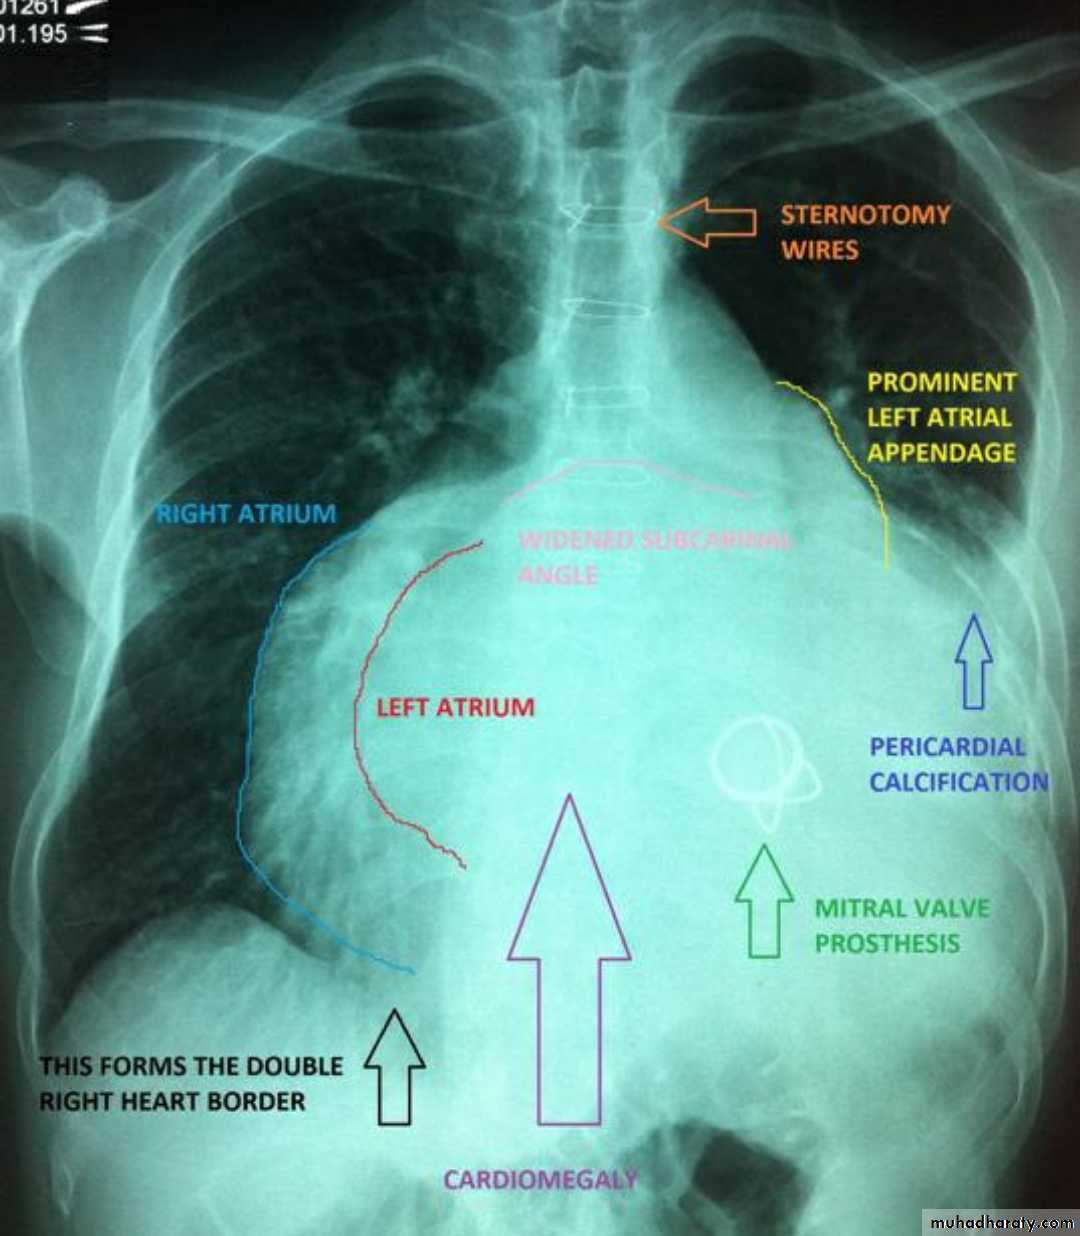

Mitral valve disease

Mitral valve disease (double density RT cardiac border)

15.mitral valve disease & their sign

16.MVD